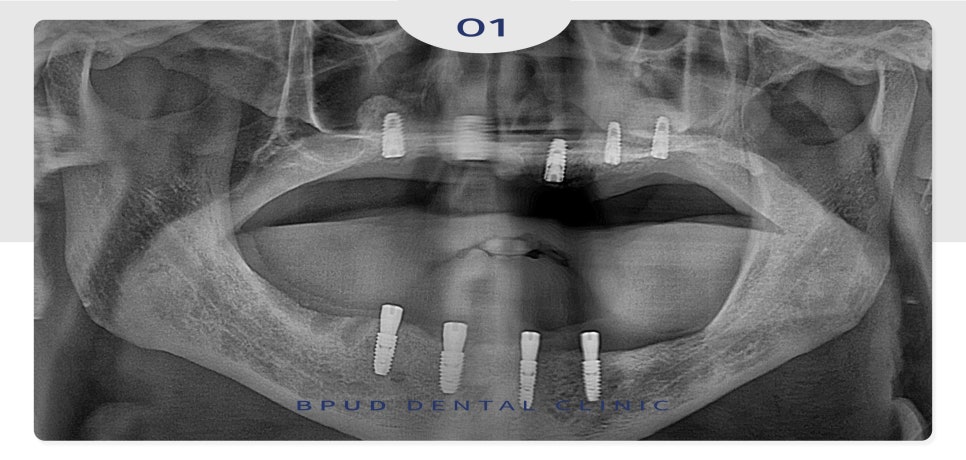

임플란트를 식립하고

3개월 후의 사진입니다.

위쪽은 양쪽 다 상악동 거상술,

비강 거상술을 통해 부족한 부분의

뼈를 이식하여 단단하게 만들어 준 뒤

5개의 임플란트를 식립하였고

아래쪽도 심한 골흡수로 인해

신경과의 거리가 약 3~5mm 안 나올 정도로

매우 가까워 4개를 식립하였는데

유지가 아주 잘 되고 있는 모습입니다.